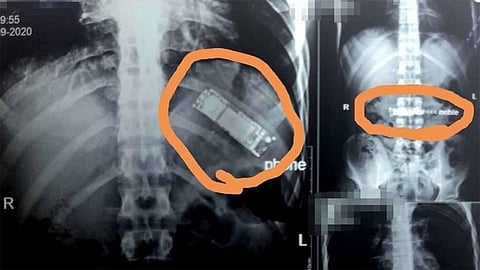

وأظهرت الفحوصات أن هذا الجسم الغريب هو هاتف جوال، فيما قال المريض إنّه ابتلعه خلال لحظة مزاح بينه وبين زملائه، لافتًا إلى أنه لم يبلغ أسرته بالواقعة ظنًا منه أنه وبمجرد أن يقوم بالقيء في أي وقت سيتمكن من إخراج الهاتف من معدته.

وأجرى الفريق الطبي جراحة عاجلة للمريض، استغرقت ساعتين واستخرج الهاتف من معدته. فيما اعتبر الأطباء أن «القدر كان رحيمًا بالمريض حيث لم تتحلل البطارية وتتفاعل داخل جسمه وتصيبه بالتسمم».